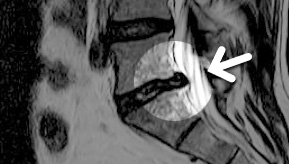

MRI

ϰ ڻ ͼ ̶ ؿ.

ü Ƶ ̰ ȣ µ

㸮 , ٸ ʹ

, Ƹ, ߰ ļ

ũ Ŀ